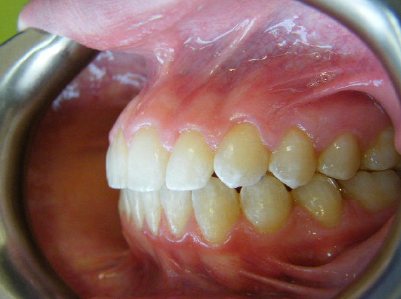

Patient 2: Significant increased overjet and upper and lower crowding.